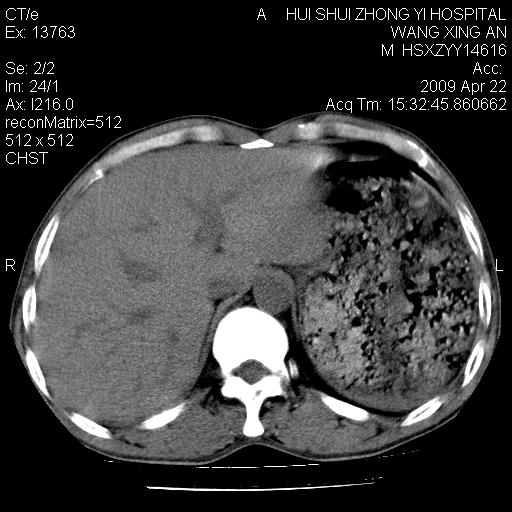

标题: CT19534:患者男、46岁咳嗽、胸痛半月。 [打印本页]

标题: CT19534:患者男、46岁咳嗽、胸痛半月。

1、右下肺中央型肺癌并右肺转移,右肺下叶不张。(肿块围绕右肺下叶支气管生长,致管腔闭塞右肺下叶不张;右肺有结节影)。

2、右侧胸腔积液。

3、右中上肺陈旧性肺结核(右肺见纤维化病灶及点状钙化)。

1、右下肺中央型肺癌并右肺转移,右肺中下叶不张。(右肺有结节影)。胸骨转移